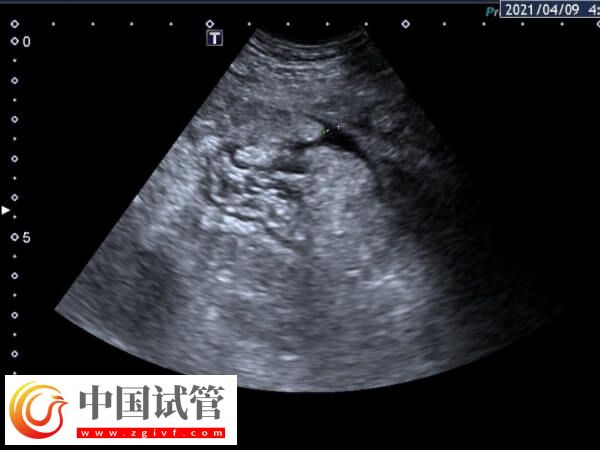

取卵手術(shù)后,女性可能會出現(xiàn)卵巢過度刺激綜合征(OHSS),這是一種常見的并發(fā)癥,表現(xiàn)為腹水。建議及時(shí)就醫(yī),進(jìn)行詳細(xì)的體檢和必要的實(shí)驗(yàn)室檢查,以評估腹水的嚴(yán)重程度,并根據(jù)醫(yī)生的建議進(jìn)行相應(yīng)的治療即可。